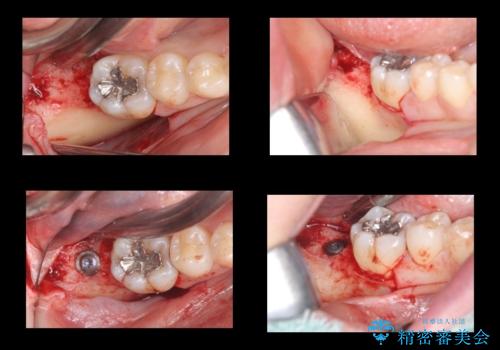

合計3本の奥歯を抜歯したところに、インプラント治療を行っています。

また、左上奥歯の根の治療および右下の虫歯治療も併せて行っています。

外科手術時には麻酔医により静脈内鎮静法を行っています。

静脈内鎮静法は、手術時の記憶がなくなり、うたた寝をしたような状態で手術を終えられるため、恐怖を味わうことなく手術を受けることが可能です。